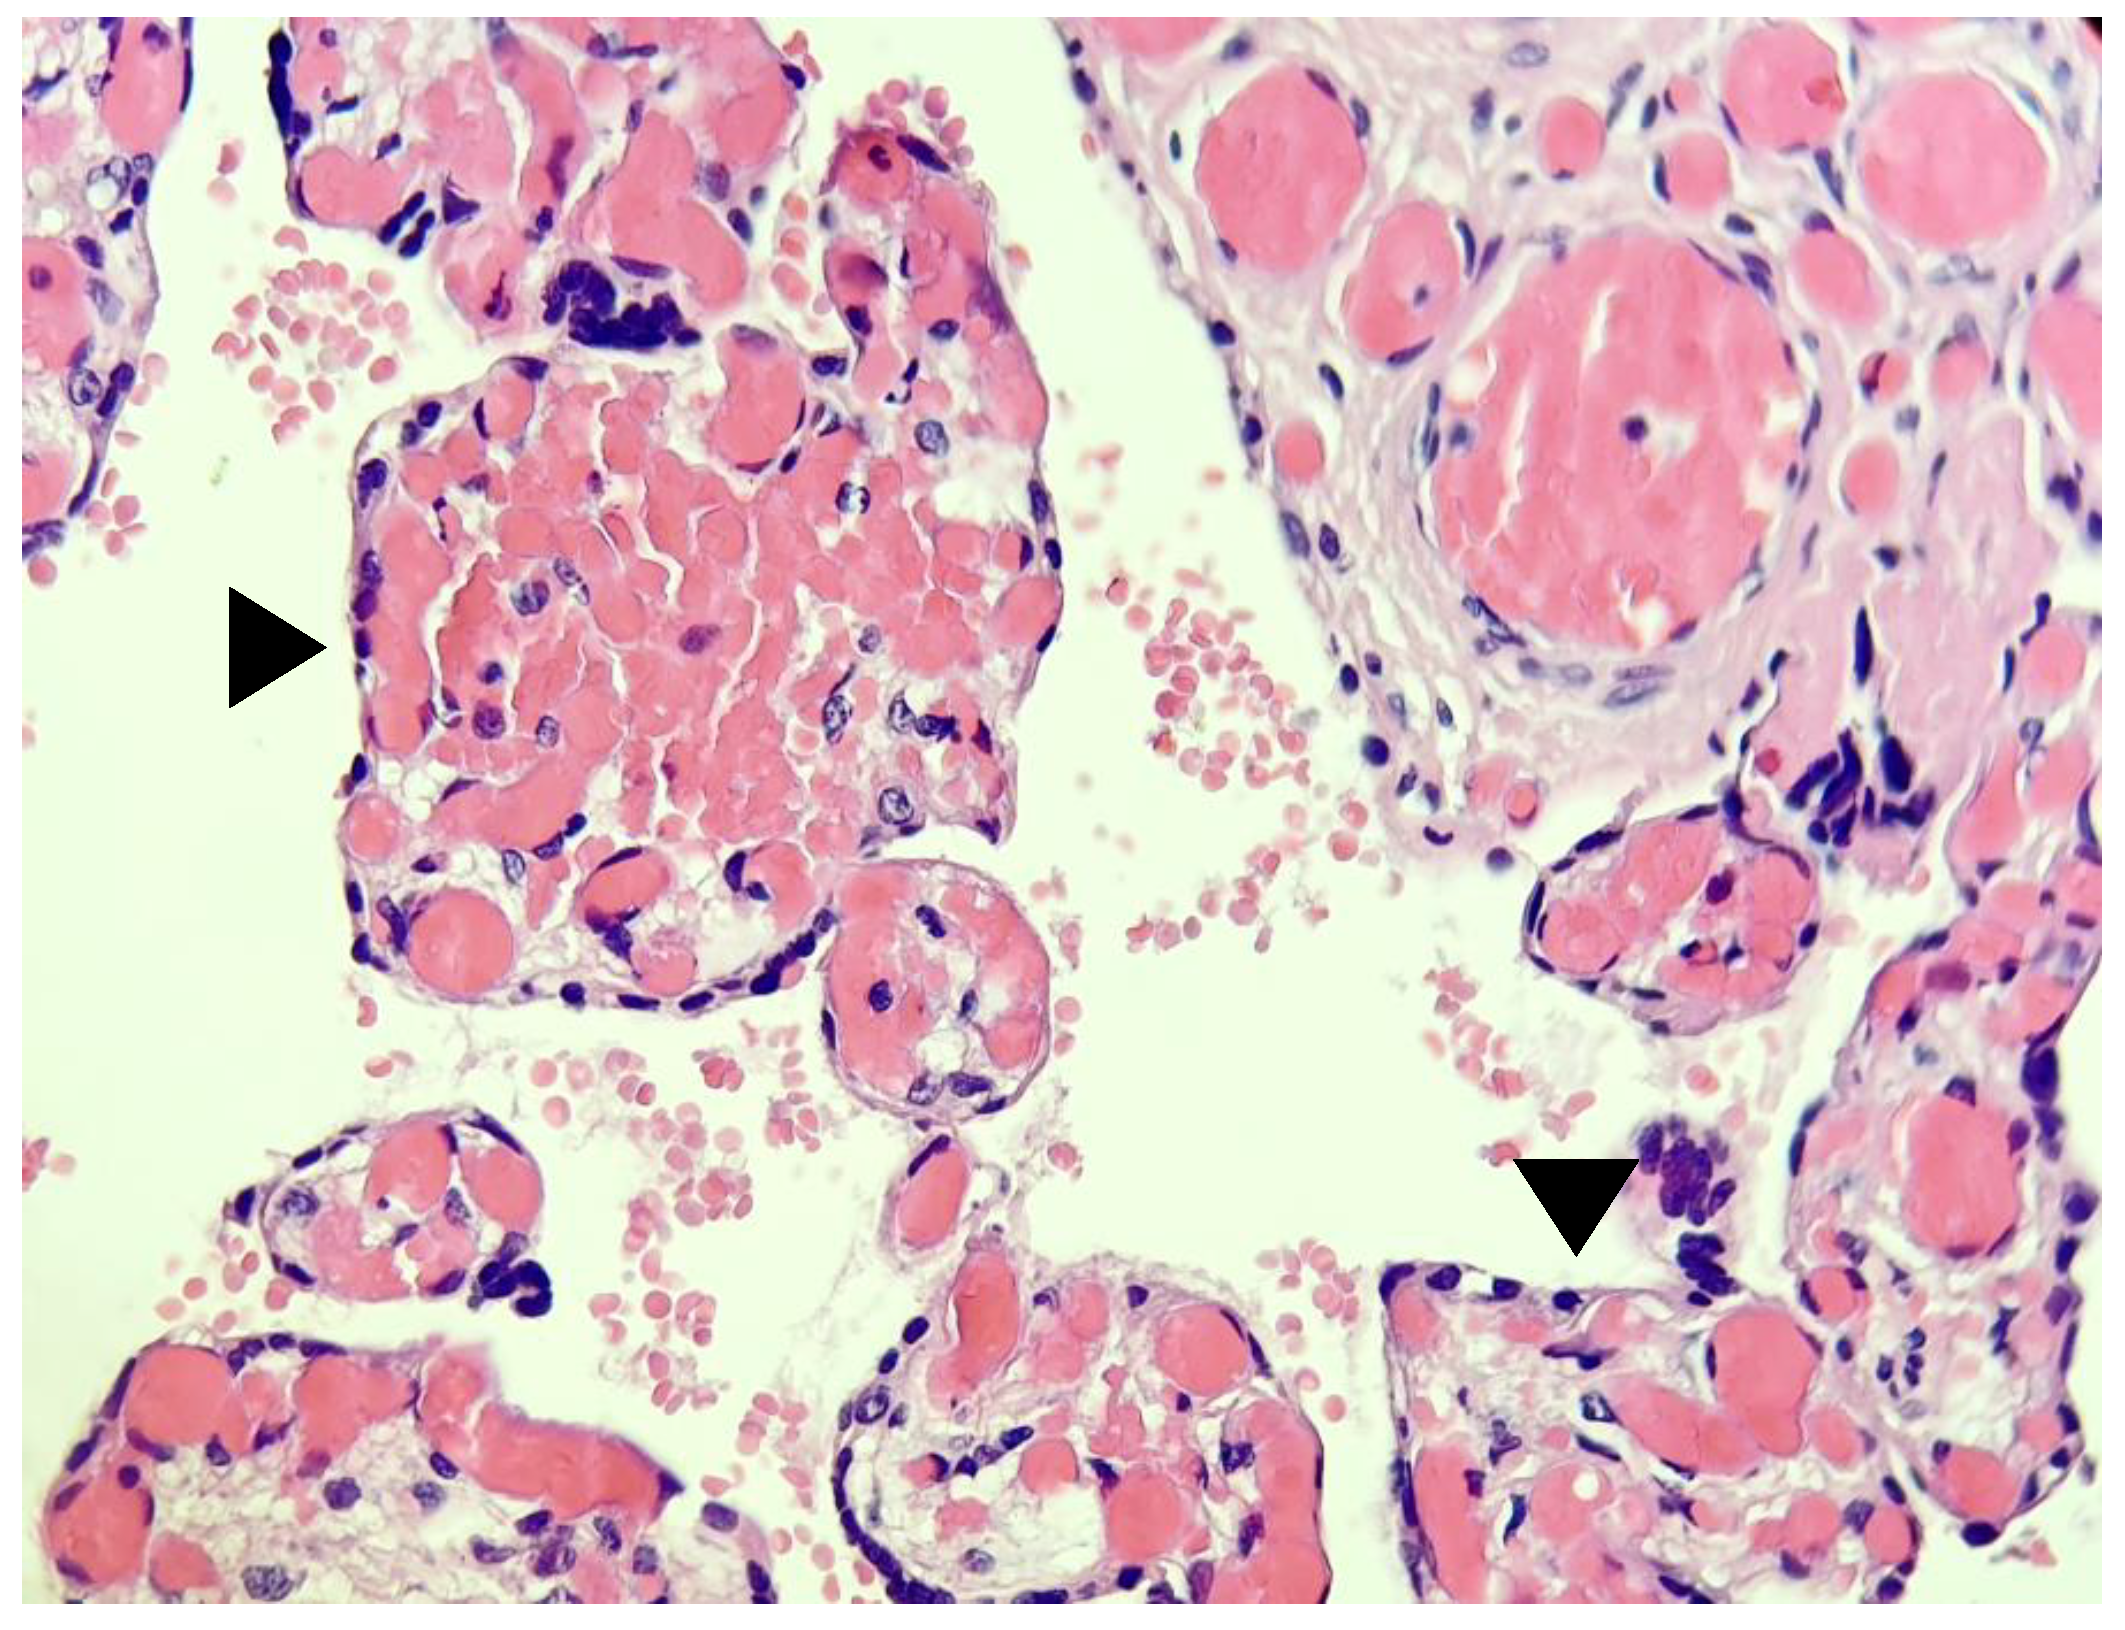

- Shanes, E.D.; Mithal, L.B.; Otero, S.; Azad, H.A.; Miller, E.S.; Goldstein, J.A. Placental Pathology in COVID-19. Am. J. Clin. Pathol. 2020, 154, 23–32. [Google Scholar] [CrossRef] [PubMed]

- Husen, M.F.; van der Meeren, L.E.; Verdijk, R.M.; Fraaij, P.L.A.; van der Eijk, A.A.; Koopmans, M.P.G.; Freeman, L.; Bogers, H.; Trietsch, M.D.; Reiss, I.K.M.; et al. Unique Severe COVID-19 Placental Signature Independent of Severity of Clinical Maternal Symptoms. Viruses 2021, 13, 1670. [Google Scholar] [CrossRef] [PubMed]

- Jaiswal, N.; Puri, M.; Agarwal, K.; Singh, S.; Yadav, R.; Tiwary, N.; Tayal, P.; Vats, B. COVID-19 as an independent risk factor for subclinical placental dysfunction. Eur. J. Obstet. Gynecol. Reprod. Biol. 2021, 259, 7–11. [Google Scholar] [CrossRef]